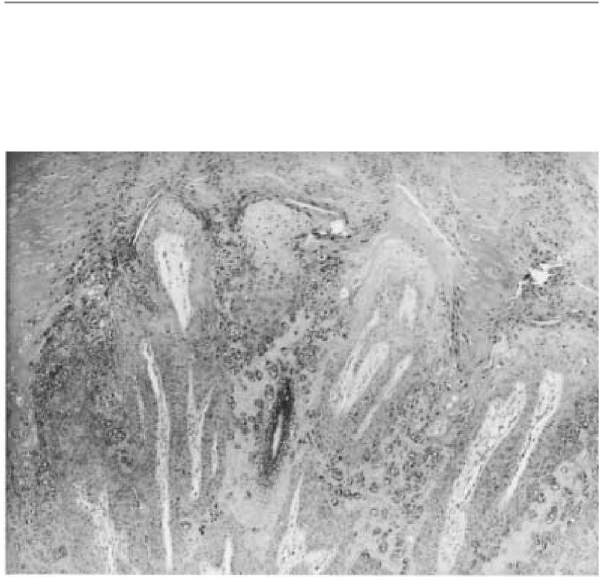

445. A fotomicrografia abaixo é de uma pequena lesão papilar encontrada na

superfície dorsal da mão esquerda de um jovem de 18 anos. Descreva a

aparência microscópica desta lesão.

445. A resposta é d. (Silverberg, p. 195. Cotran, pp. 1208–1209. Rubin, pp. 1288–

1289.)Verrugas(verrugas)sãolesõescutâneascausadasporpapilomavírus humanos

(HPVs) que pertencem ao grupo dos papovavírus contendo DNA.

Asverrugassãoclassificadasdeacordocomsualocalizaçãoemorfologia.Verruca

vulgaris, o tipo mais comum de verruga, pode ocorrer em qualquer parte do corpo,

mas mais comumente está localizado nas superfícies dorsais das mãos. O fo-

A tomicrografia revela características de verrugas vulgares,

incluindohiperqueratose,hiperplasiapapilardaepidermeenumerososgrandes

grânulos de queratohialina dentro das células epidérmicas. Verrucae vulgaris

temtem sido associada a vários tipos de HPV, incluindo os tipos 2 e 4. Plantar